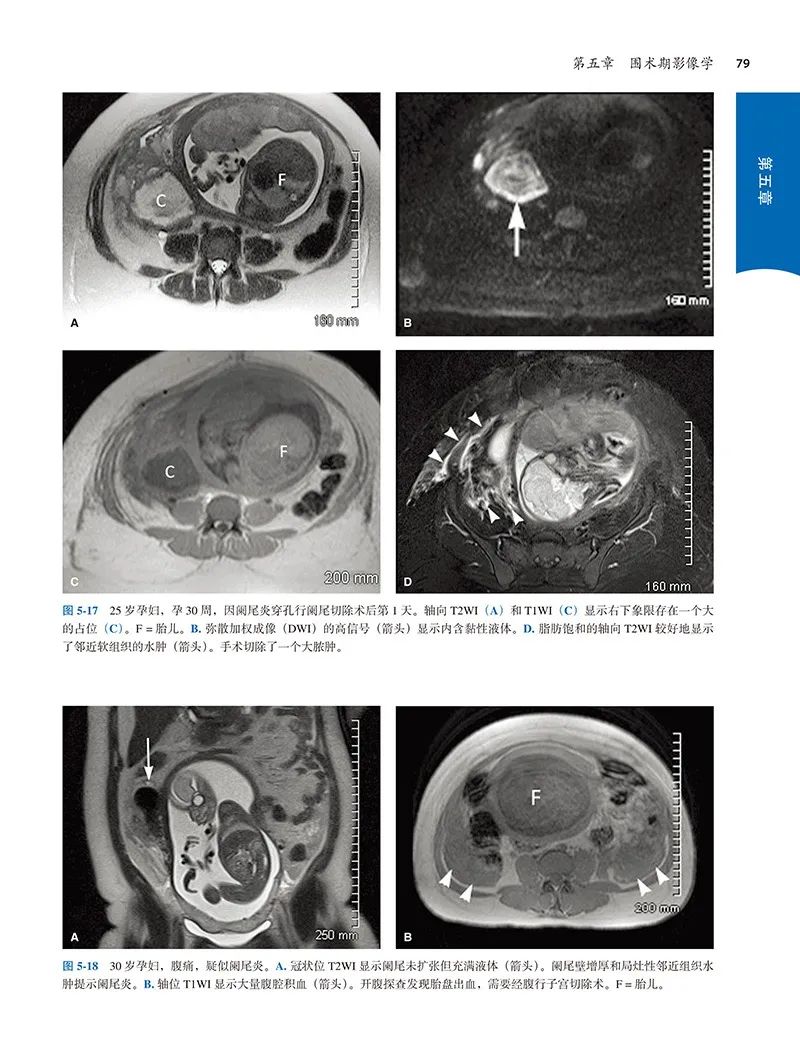

本书是一本介绍产科手术的书,分为基础知识、产前、产时和产后四个部分。本书从解剖学、产科各种常见手术操作技术、围手术期评估及常见并发症处理等多角度、全方位进行阐述,还针对临床模拟教学、手术相关影像学检查、宫内治疗、孕期腹腔镜手术等特殊情况进行了详细讲解,主题涵盖与产科手术相关的各个领域,内容全面而具体,既讲述了历史沿革发展和应用现状,又介绍了的临床进展。全书共计引用3000余篇参考文献,数据详实可靠,同时通过674个插图(包括超声图像、核磁共振图像、实物照片、显微照片和数据图)对手术器械、操作步骤及模拟情景进行了生动的呈现,图文并茂。无论是在资源不足的基层医院抑或是设备齐全的三级医院工作的医生,无论是对妇产科研究生、住院医师,还是基层医院进修医生,这部著作都有很大的参考和学习价值。